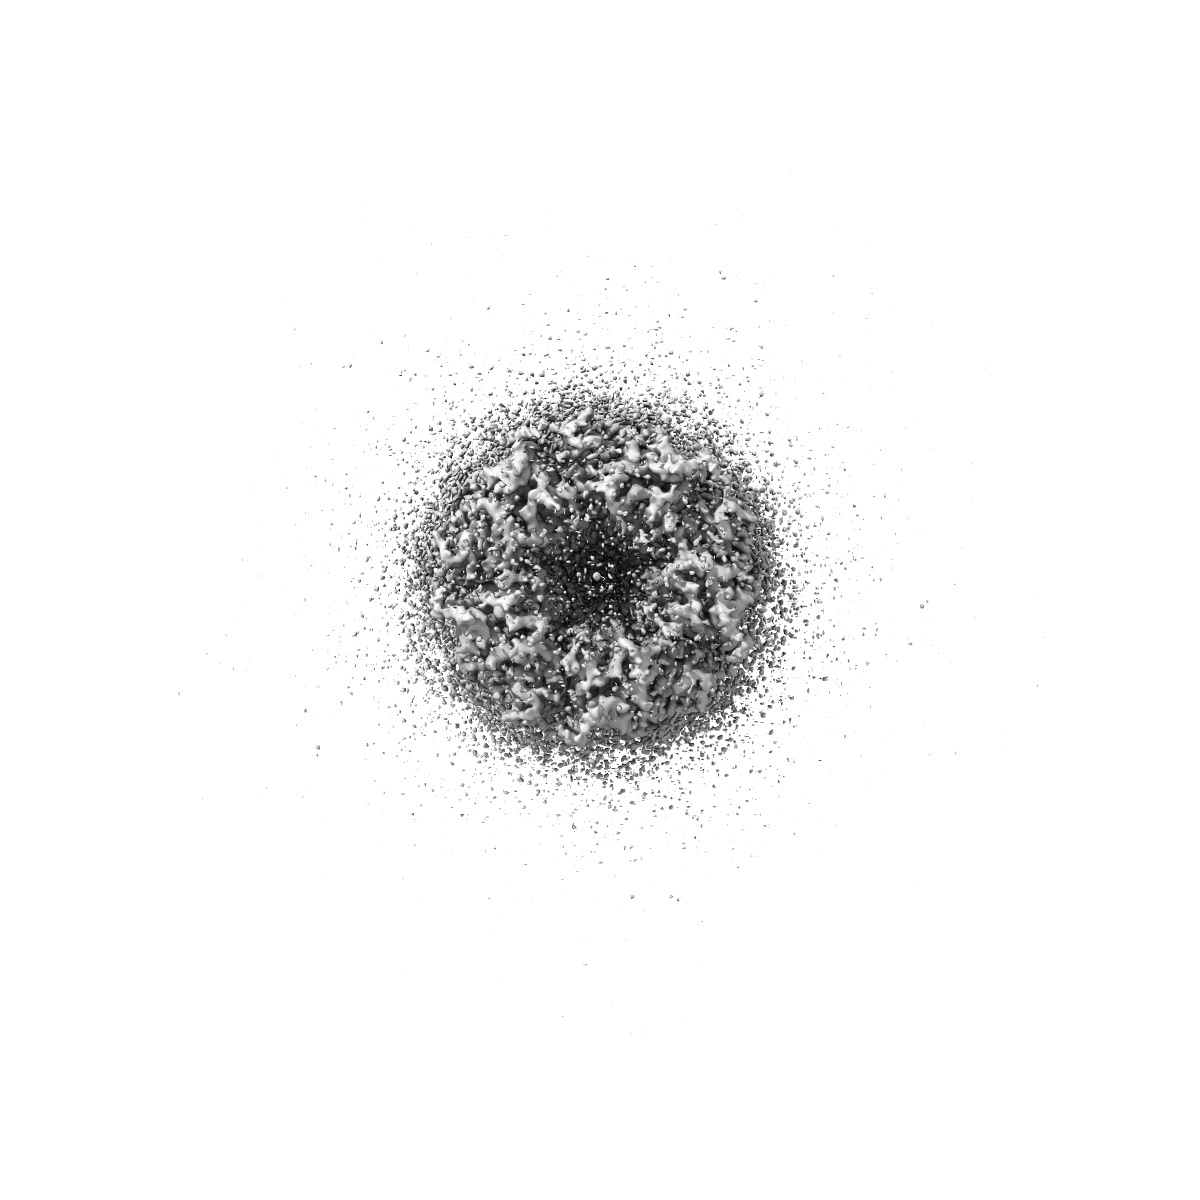

CryoEM structure of human rho1 GABAA receptor in complex with (R)-GABOB in the primed state

Sample: human rho1 GABAA receptor

Cryo-EM structures of rho 1 GABA A receptors with antagonist and agonist drugs.

Fan C , Cowgill J , Howard RJ , Lindahl E

(2025) Nat Commun , 16 , 7077 - 7077